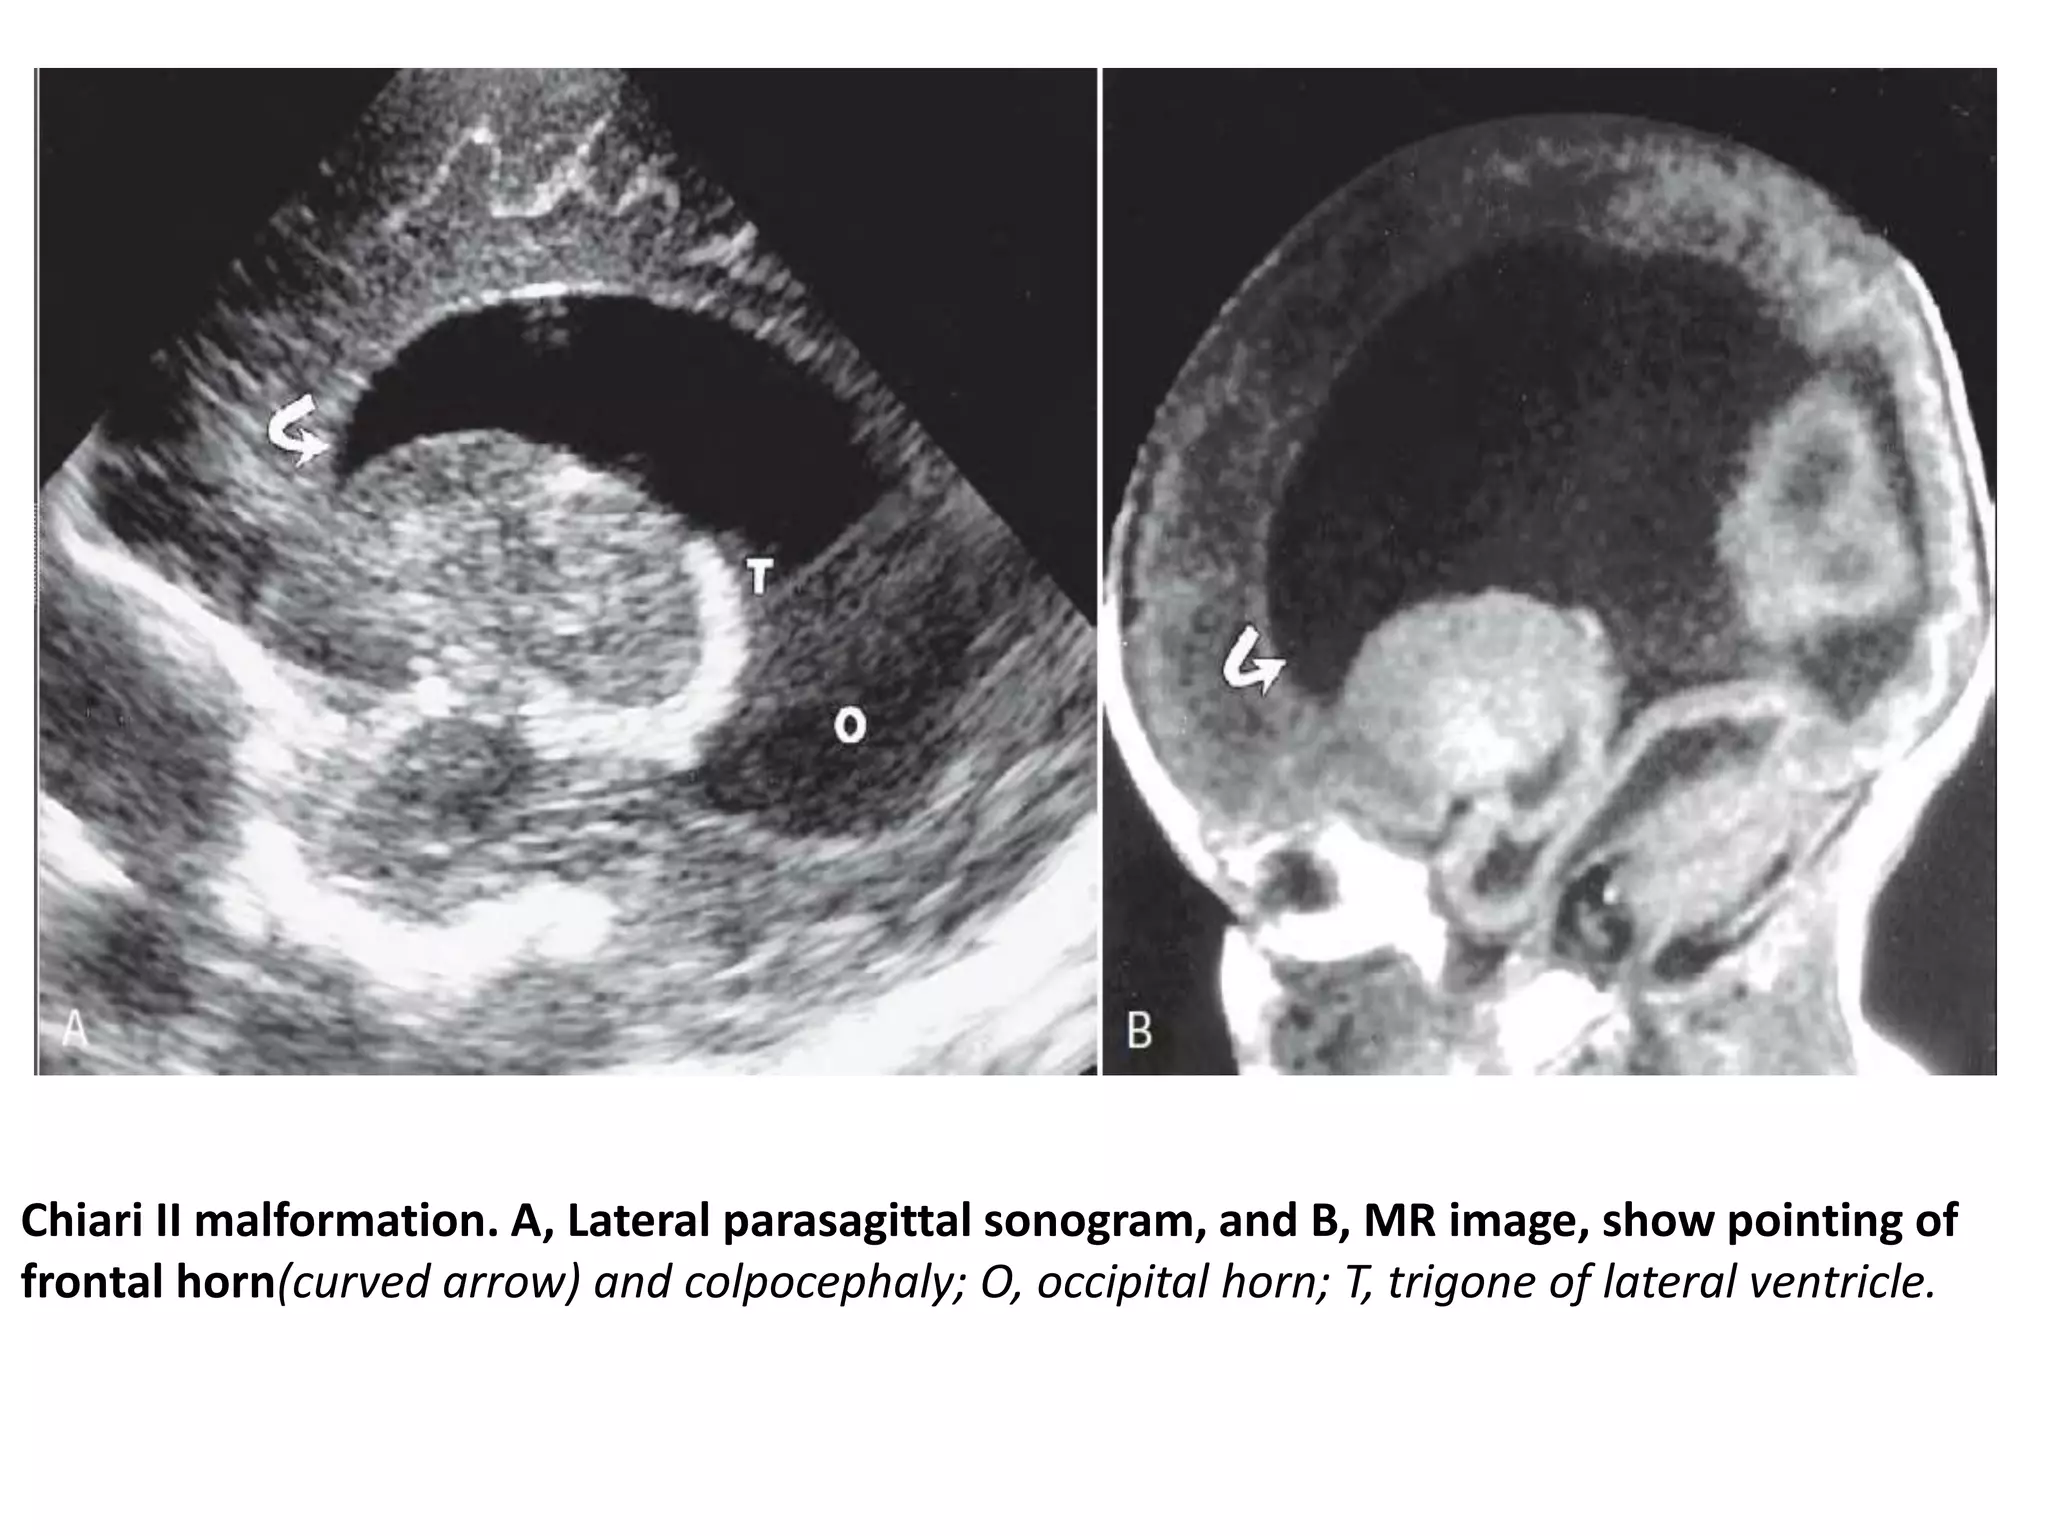

Chiari II malformation

• the most common and of greatest clinical importance

because of its almost universal association with

myelomeningocele.

Chiari II malformation. A, Lateral parasagittal sonogram, and B, MR image, show pointing of

frontal horn(curved arrow) and colpocephaly; O, occipital horn; T, trigone of lateral ventricle.

Chiari II malformation.A, Lateral parasagittal sonogram, and B, MR image, show pointing of frontal horn(curved arrow) and colpocephaly; O, occipital horn; T, trigone of lateral ventricle.